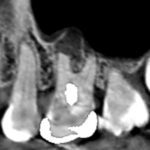

矢印の先が上顎第一大臼歯です。精密根管治療により膿の改善をはかりました。石灰化を顕微鏡下で除去し、根管充填しました。画像は、根管充填のレントゲン画像です。